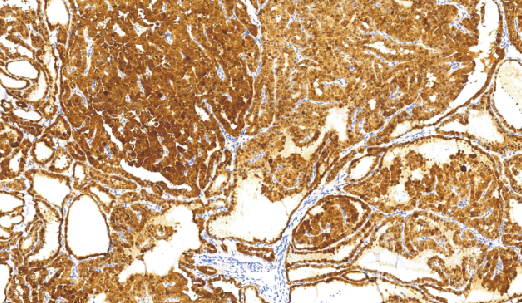

Galectin-3(Gal-3)免抗人半乳凝集素-3单克隆抗体

Galectin-3是B牛乳糖镶嵌外源凝集素家族中的成员之一Galectin-3涉及几种生物学活动,包括镶嵌到基底膜糖蛋白层粘连蛋白内。细胞表面的Galectin-3可能涉及同型细胞的粘附并且在结肠癌进展中下调。在乳腺癌中也检测出这种下调,有相似的表达相关性报道。Galectin-3下调可能是使癌细胞与层粘连蛋白相互作用,从而促使癌细胞浸润和转移的许多作用机制之一,而且在多种类型肿瘤中已证实其活化浸润表型。据报道,在间变性大细胞淋巴瘤中检测到Galectin-3,但在不同类型的何杰金氏病或者RS细胞中没有检测到Galectin-3。

- 阳性部位:胞膜,胞质

- 适用组织:石蜡切片

- 预处理:热修复